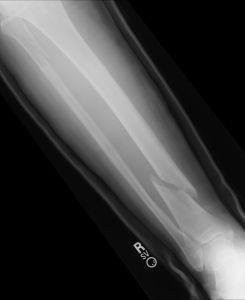

Bizonyos esetekben a csonttöréssel járó balesetek után is szükség van rehabilitációra, törés utáni gyógytorna alkalmazására. Ilyenkor fontos, hogy először terhelésmentesen történjen a torna és csak később, fokozatosan térjünk át az erősítő gyógytorna feladatokra. Kevésbé súlyos esetekben, nagy odafigyeléssel, ortopéd gyógytornász által előírt feladatokkal a terápia, a csonttörés utáni gyógytorna otthon is elvégezhető, de komoly esetekben mindenképpen manuálterapeuta közvetlen segítségére van szükség. A gyogytorna karra és lábra is egyaránt hatékony.